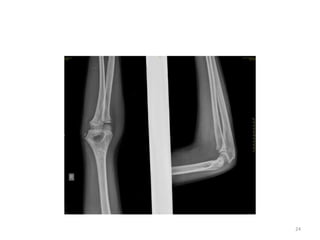

Elbow joint

• Secondary ossification Centres : (3 bones; 6 Ocs)

Capitulum (C) - appearance - 1 year of life

Head of Radius (R)– appearance -4 to 5 years

Medial Epicondyle (ME)

Appearance – 5 to 6 years

Fusion – 16 to 17 years

Trochlea (T) – appearance – 9 to 11 years

Olecranon Process of Ulna (OP)

Appearance - 8 to 9 years

Fusion- 16-17 years

Lateral Epicondyle(LE) – 11 to 12 years

Conjoint (Composite)Epiphysis (CE) [fusion of C+T+LE]

Formation – 14 to 16 years

Fusion – 16-17 years

Note: Fusion of O.Centres at elbow joint is 16-17 years in male, 15-16 years in female

Elbow joint • Secondaryossification Centres : (3 bones; 6 Ocs) Capitulum (C) - appearance - 1 year of life Head of Radius (R)– appearance -4 to 5 years Medial Epicondyle (ME) Appearance – 5 to 6 years Fusion – 16 to 17 years Trochlea (T) – appearance – 9 to 11 years Olecranon Process of Ulna (OP) Appearance - 8 to 9 years Fusion- 16-17 years Lateral Epicondyle(LE) – 11 to 12 years Conjoint (Composite)Epiphysis (CE) [fusion of C+T+LE] Formation – 14 to 16 years Fusion – 16-17 years Note: Fusion of O.Centres at elbow joint is 16-17 years in male, 15-16 years in female 35

ELBOW JOINT All OCsAppeared and fused (>16-17 years) 36